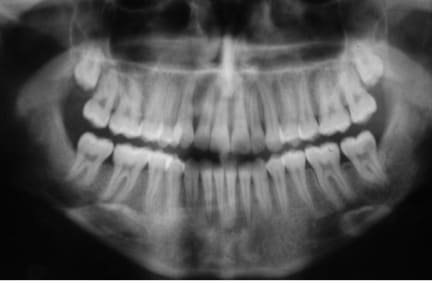

que feriez vous dans ce cas? extraire la 37 et tracter la 38 en position de la 37 ou preserver la 37 qui semble-t-il a un pronostic endodontique defavorable!

quel est le meilleur rapport benefice risque?

Extraire la 37 sans hésiter et tenter ta chance pour le tractage de 38.

Quel pronostic concernant la traction d'une sagesse quasi horizontale comme sur la pano?

La question m'interpelle, je suis en général favorable aux extractions/tractions des 8, mais c'est typiquement le cas ou j'ai un doute...

Racines fines et longues et fragiles, risque de fracture, proximité du canal dentaire, racine de la 38 fermées, mauvaise position de la 38 qui va gêner la cicatrisation osseuse, et si complications -> obligation d'extraire la 38, mouvement othodontique très important dans un os néo formé pauvre, risque important de fonte de la racine 38, longueur d'un traitement qui donnera envie de l'arrêter.

Vu l'état de la denture sur la pano, il faut mieux commencer par des choses simples, puis réévaluer la motivation, avant de se lancer dans un ttt multiattaches potentiellement cariogène.

A mon sens, on ne peut pas juger du pronostic de la 37 sans y être allé voir.

je m'occuperais d'abord de l'hygiène et des caries avant de réfléchir à l'ortho.

Verdict des prof, redresser cette dent est parfaitement faisable mais :

- surement plus d'un ans de traitement

- risque de résorption radiculaire laissant la dents avec un rapport couronne racine défavorable sur le long terme

Eux ils peuvent faire mais ça ne leur semble pas la meilleur option pour le patient, si il avait était plus jeune ça se serait discuté.

jeudi matin j'extraierai la 37 ensuite on essaiera de faire qq chose avec la 38 le patient comprend que l'issue est aleatoire donc si ca marche pas je lui poserai un implant.